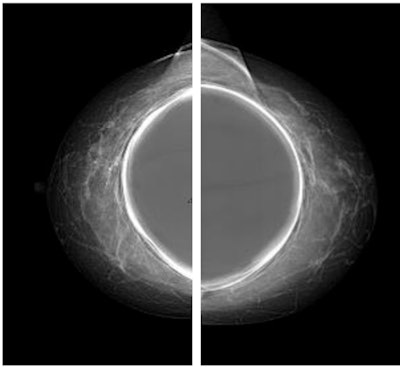

The women were divided into two groups. The first group included 15 women undergoing standard protocol with standard configuration for the automatic exposure control (AEC) algorithm present on the mammography unit, including eight projections: four with digital mammography that included the breast implant and four with tomosynthesis (with synthetic image) using the Eklund maneuver, a modified compression technique that can be used for patients with augmented or reconstructed breasts postmastectomy.

"In our patient cohort, we demonstrated that with the study in mammography mode and only four projections with prosthesis included, and using a standard exposure meter, the exam is associated with an average glandular dose of 7.5 mGy," the authors stated.

If the Eklund maneuver is also performed in tomosynthesis mode, the woman is exposed to an average of 11 mGy in total. A low-dose configuration of the AEC is associated instead with an average glandular dose equal to 9.2 mGy total. This configuration allowed a maximum amount of radiographic information currently possible, lowering the dose by 15%, while maintaining adequate image quality, they pointed out.